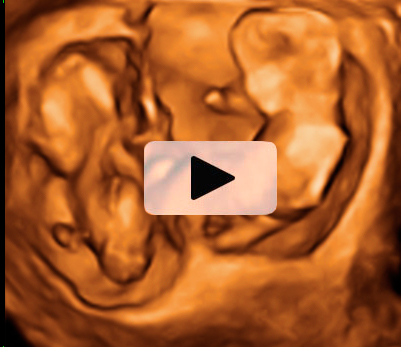

El movimiento de gemelos en el útero encierra sorpresas, como en esta ecografía 4D en la que vemos a dos hermanos en sus respectivas bolsas. El gemelo de la derecha parece estar bailando el "hula hoop" con su propio cordón umbilical, que le rodea las piernas formando un círculo. Destaca la posición casi erguida del niño dentro del útero materno, casi a punto de dar un paso. Cuando uno de los fetos genera mucho movimiento, suele arrastrar a su gemelo a que se mueva también, aunque esté adormecido.

Ecografía 4D de gemelos de 12 semanas moviéndose: el baile del "hula hoop"